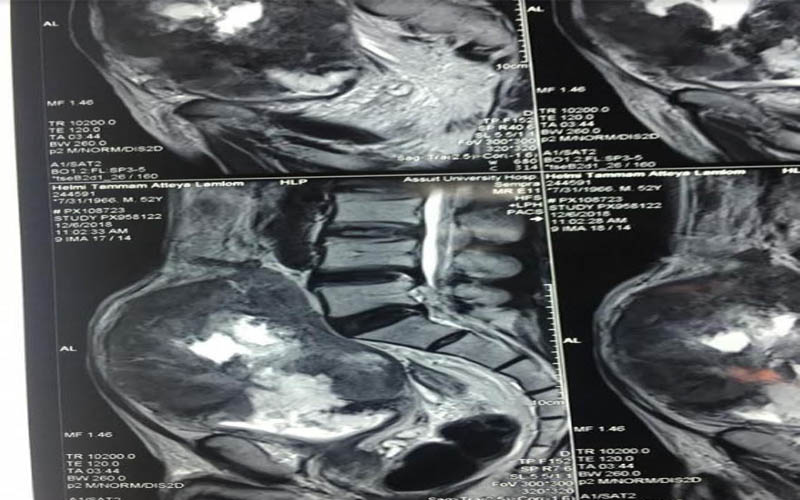

وعن تفاصيل العملية فقد أوضح الدكتور ضياء عبد الحميد الأستاذ بقسم جراحة المسالك البولية والكلى ورئيس وحدة أورام المسالك وقائد الفريق الطبي المسئول عن العملية ، أن تلك العملية تعد من أخطر عمليات استئصال أورام المثانة البولية وذلك نظراً لكبر حجم الورم واختراقه للأمعاء والأنسجة المجاورة من الشرايين والعضلات ، مما يشكل خطورة بالغة على حياه المريض والذي تم تعرضه لظروف معينة تسببت في إهماله للمرض لعدة سنوات ، مشيراً أن ذلك تم من خلال التنسيق والتعاون مع أعضاء قسم الجراحة العامة .

كما كشف الدكتور عمرو أبو فدان المدرس بقسم جراحة المسالك وعضو الفريق الطبي المسئول عن العملية انه فور وصول المريض إلى المستشفى تم خضوعه لعدد من الإشاعات والفحوصات الأولية والتي بينت تضخم حجم الورم مما يستلزم التدخل الجراحي لفصل الورم عن الأنسجة المحيطة وإنقاذ حياه المريض وبالفعل تم إجراء الجراحة بنجاح وخرج المريض من غرفة العمليات دون أي مضاعفات كما تم متابعة الحالة فى غرفة العناية المركزة لمدة 24 ساعة وعند استقرار حالة المريض تم نقله إلى غرفته بمستشفى جراحة المسالك البولية والكلى ، وفى السياق ذاته نوه أن نجاح العملية تم بفضل تضافر جهود الفريق الطبي بقسم جراحة المسالك البولية والكلى وعلى رأسه الدكتور حسنى البهنساوى الأستاذ المساعد بالقسم ، ومدرسين القسم وهم الدكتور أيمن عاصم ، و محمد أسامه ، وعمرو عصام ، والمعيد محمد عماد الدين ، إلى جانب فريق التخدير بقيادة الدكتور محمد أنور المدرس بقسم التخدير والعناية المركزة .